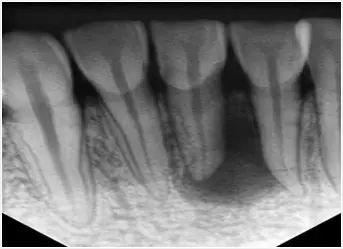

1、术前拍摄X线片 在根管治疗过程中,在根管治疗术前拍X线片,以帮助诊断,了解髓室的位置和根管数目及形态,测量根管工作长度及日后随访和评价疗效提供对比的依据。

3、确定根管工作长度 应用平行投照X线方法、根管长度测量仪确定根管度,最好插针拍X片。

6、根管充填 封闭整个根管系统、堵塞主根管和侧副根管出口、防止微生物和液体的渗漏。无论是侧方加压法还是垂直加压法,应做到根管充填致密,根管充填后X线片上无根管腔隙,也不能超出根尖孔。

患者疑问:不过,怎样才能算根管治疗成功呢? 牙医介绍说,根管治疗后,一般从患者自觉症状、到医院拍X片,检查是可以确定是否成功的。 自觉症状:无不适,咀嚼功能正常,对治疗结果、过程、患牙功能、外形满意。 X片:牙周膜间隙正常或轻度增厚,原有根尖病变缩小或消失;根尖未发育完全者,术后3—6个月逐渐形成;根管三维充填,根充物距根尖0.5—2.0mm。 临床检查:无叩痛、无窦道或窦道在治疗后1—2周内闭合。